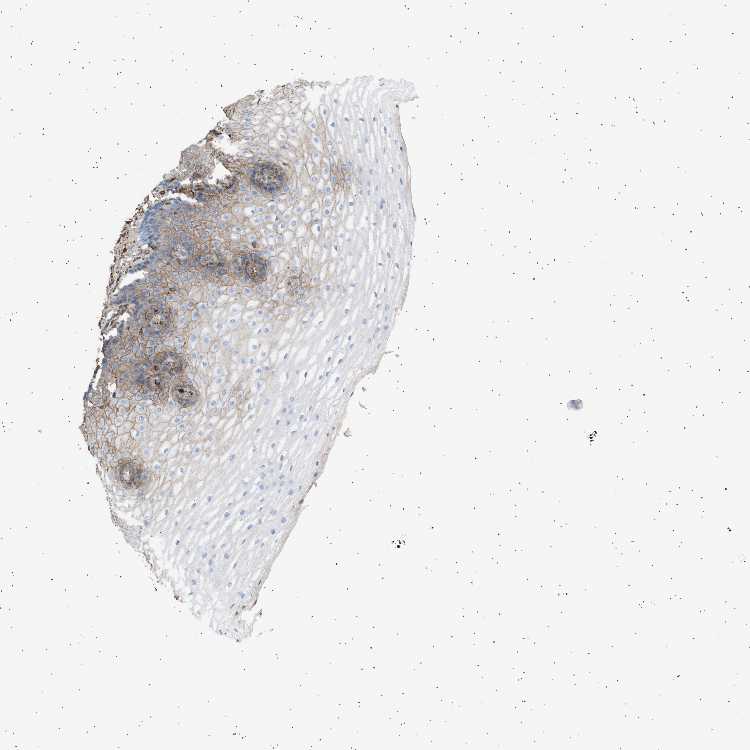

ESOPHAGUS - Antibody stainingi

Antibody staining in the annotated cell types in the current human tissue is reported as not detected, low, medium, or high, based on conventional immunohistochemistry profiling in selected tissues. This score is based on the combination of the staining intensity and fraction of stained cells.

Each image is clickable and will lead to virtual microscopy that enables deeper exploration of all samples and also displays staining intensity scores, fraction scores and subcellular localization as well as patient and tissue information for each sample.

Antibody HPA060604Antibody CAB016072

Squamous epithelial cells Not detectedLow